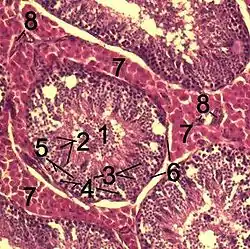

Spermatocyty I. řádu, nazývané i primární spermatocyty, můžeme najít ve vrstvě nad spermatogoniemi. Tyto buňky jsou největšími buňkami, které jsou v semenném epitelu. Brzy po svém vzniku vstupují spermatocyty I. řádu do profáze prvního redukčního dělení. Tímhle krokem je zahájena meióza.[2] V tuto chvíli obsahuje primární spermatocyt 46 (44 + XY) chromozomů a 4N DNA (N značí buď haploidní set chromozomů [23 u člověka], či množství DNA v tomto setu obsažené). Buňka prochází během profáze čtyřmi stádii: leptotenním, zygotenním, pachytenním, a diplotenním. Dospívá až do stadia diakineze, ústící v separaci chromozomů.[3] Profáze I. zracího dělení je dlouhá, trvá 22 dní. V semenném epitelu proto nacházíme četné spermatocyty I. řádu.[2] V těchto stadiích meiózy dochází k překřižování ramének chromozomů (tzv. crossing-over). Poté vstupuje buňka do metafáze a v následující anafázi putují chromozomy k protilehlým pólům. Jádra spermatocytů I. řádu jsou charakterizovaná přítomností chromozomů v různých fázích spiralizace.[3]

Spermatocyty II. řádu, nebo také i sekundární spermatocyty, obsahují pouze haploidní počet chromozomů 23 [2] (22 + X nebo 22+ Y)[3]. Toto omezení jejich počtu (z 46 na 23) je doprovázeno snížením množství DNA v buňce (z 4N na 2N). Sekundární spermatocyty obsahují sférické jádro bez jadérek a mají cytoplazmu bohatou na ribozomy. Jsou uloženy ve 2-3 vrstvách v blízkosti lumen semenotvorného kanálku.[2] Spermatocyty II. řádu zastihneme v řezech jen zřídka, protože jsou to buňky existující jen krátce, které zůstávají v interfázi jen malou chvíli a pak rychle vstupují do druhého meiotického dělení. Tímto dělením z nich vznikají spermatidy. Spermatidy jsou buňky, které obsahují 23 chromozomů.[3] Vzhledem k tomu, že mezi prvým a druhým meiotickým dělením neprobíhá žádná S-fáze (syntéza DNA), je množství DNA v buňce zredukované na polovinu, čím vznikají haploidní (1N) elementy.[3][4] Můžeme tedy říct, že výsledkem celého meiotického procesu jsou tedy buňky s haploidním množstvím chromozomů. S oplozením se pak navracejí k normálnímu diploidnímu počtu. Meióza tedy zaručuje svou redukční povahou konstantní (fixní) počet chromozomů každého živočišného druhu.[3]